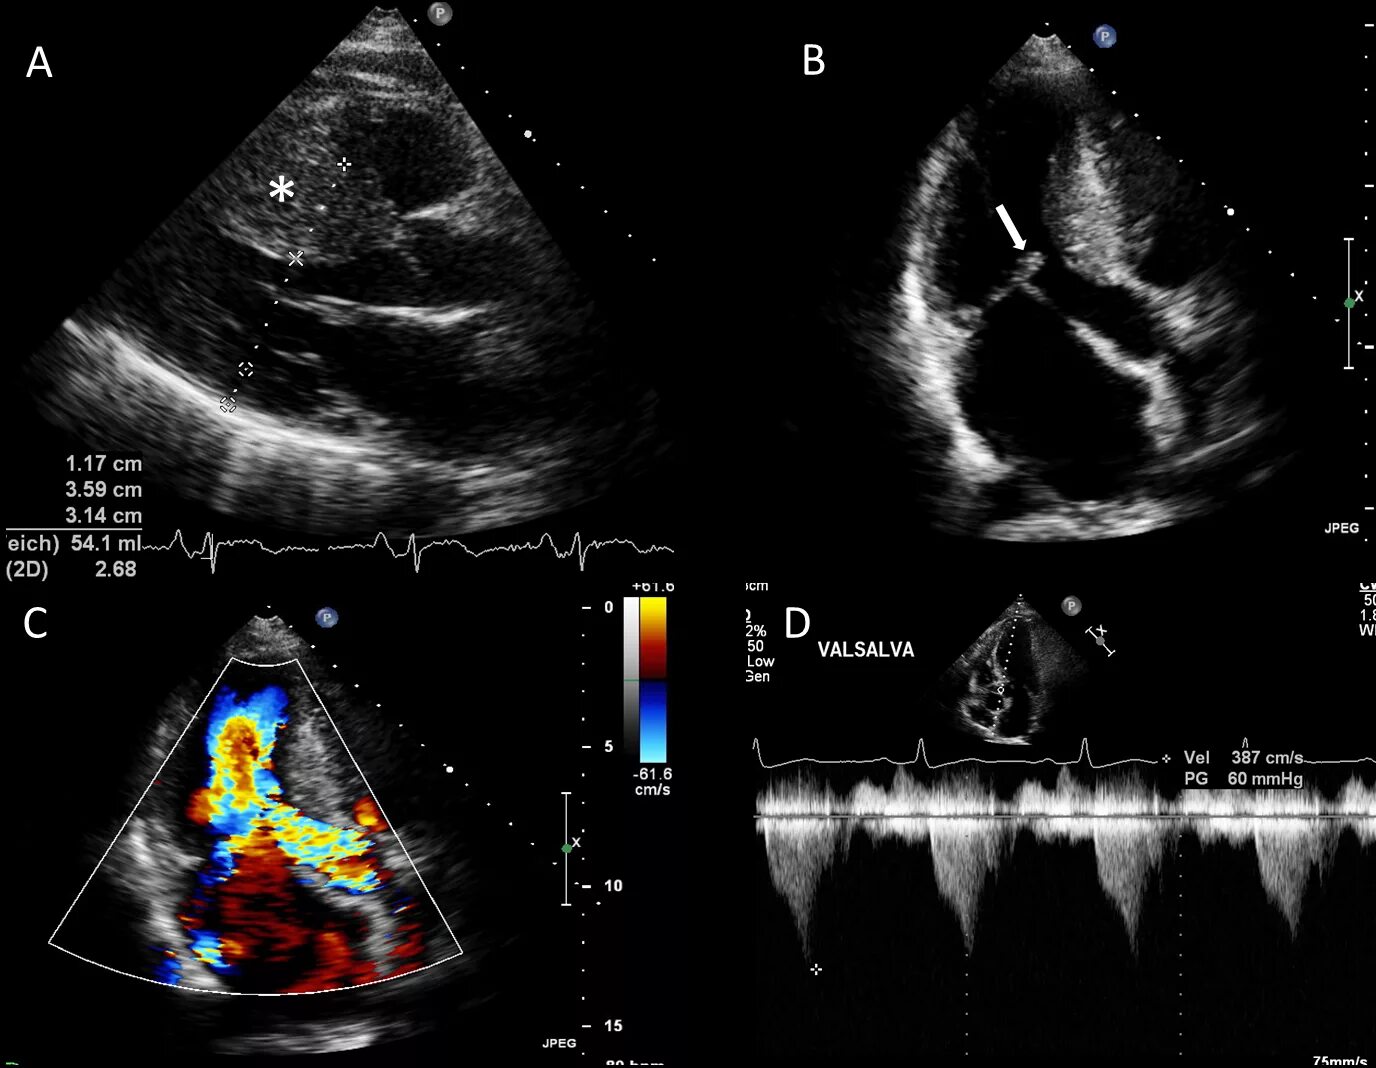

Детское эхо сердца